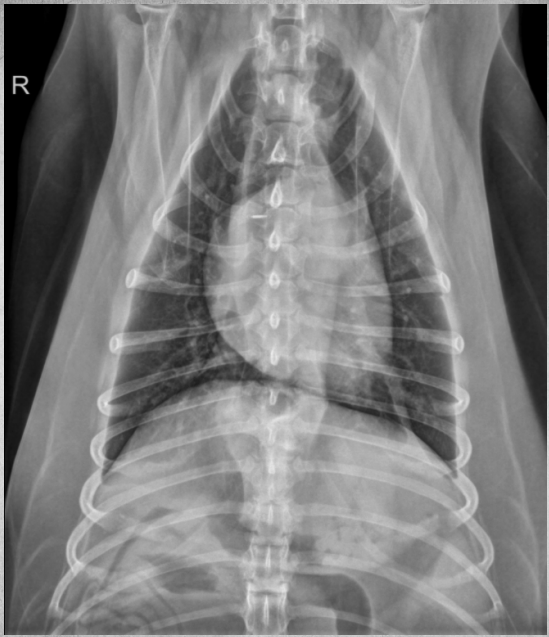

● 12 yo male castrated Shih-Tzu

● Geriatric check-up

● No clinical signs

congenital peritoneal-pericardial diaphragmatic hernia

these intestines are filled with gas due to

being empty

gastric axis also altered